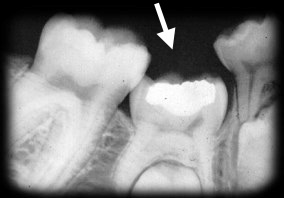

Right BW radiograph Chris M (courtesy of Dr. BM Cleghorn, Dalhousie University).

|